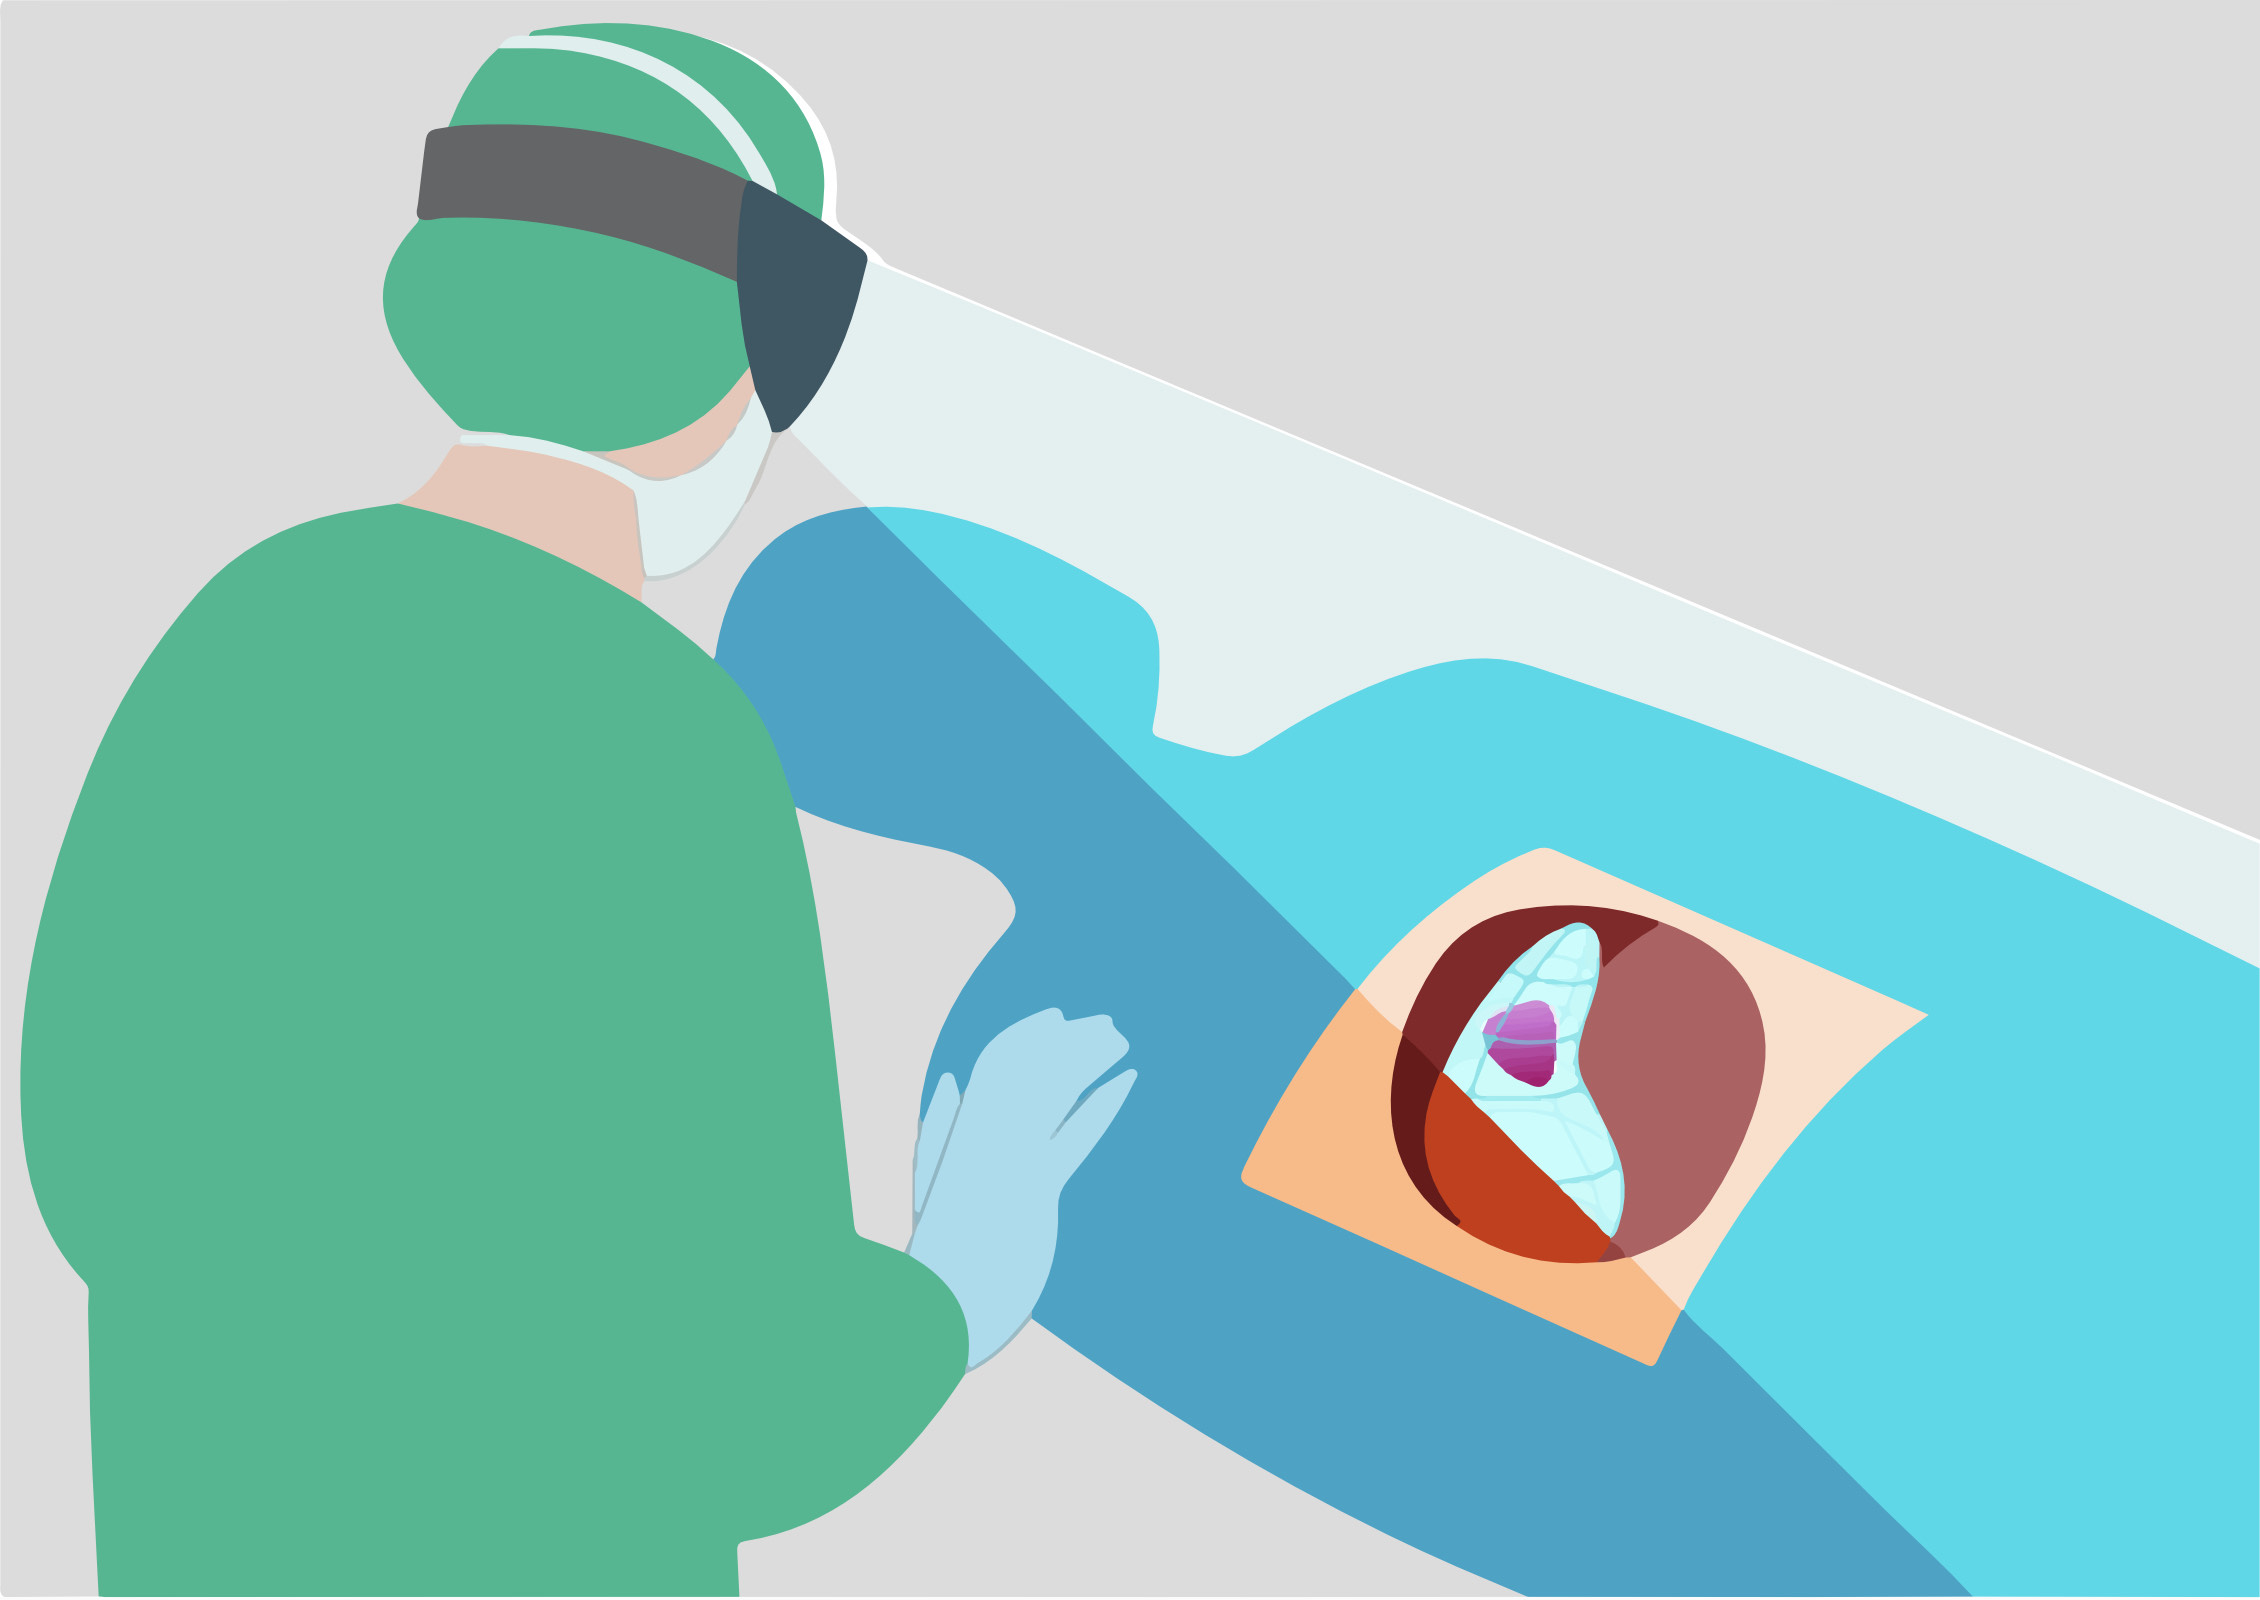

Intraoperative AR guided photoplethysmogrpahic visualization of tissue perfusion

The optimal perfusion of kidney grafts is vital for the long-term outcome after kidney transplantation. Perfusion can be influenced by the placement of the organ in the retroperitoneal space. Using photoplethysmographic visualization tools, minimal changes in color, that cannot be detected by the human eye, should be made visible and give an idea about the quality of organ perfusion. This technology should be made available to the surgeon in the operating room as a mixed reality tool, so an optimal placement of the graft can be achieved in less time and with more security.